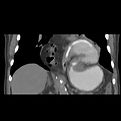

CT scan

Laparoscopic repair is the standard operation for repairing POH, which

includes reducing the content of the hernia back into the abdomen,

dissecting the hernial sac of the posterior mediastinum and reducing it

fully into the abdomen (not necessary to be removed from the abdomen),

closure of the hiatal defect (the diaphragm defect through which the

hernia protrudes into the chest) with sutures or mesh. A front wrap

(Dor Fundoplication) is usually performed to fix the stomach to the

under surface of the diaphragm that helps reduce the recurrence of POH

and provides an anti-reflux measure as well. The diagram shows the

site of the wounds. You will also have an abdominal drain from the left

abdominal side and nasogastric tube [NG] (a tube inserted through

your nostril in to the stomach to decompress it).